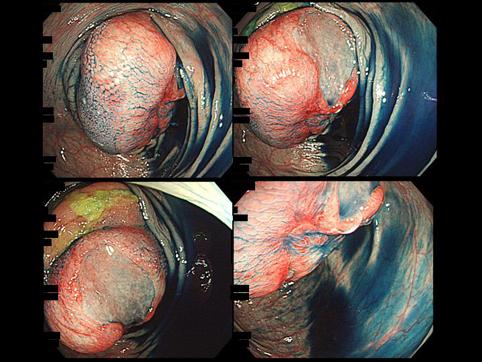

症例提示(所在地,施設名等): 福岡県・ 国家公務員共済組合連合会 浜の町病院 (松浦隆志先生からの提供症例)

疾患(病理主体)の分類悪性リンパ系腫瘍/悪性リンパ腫

部位(臓器別)小腸/回腸

検査方法内視鏡

腫瘍の肉眼分類1型(腫瘤型)/

病変の最大径(ミリ)35〜40